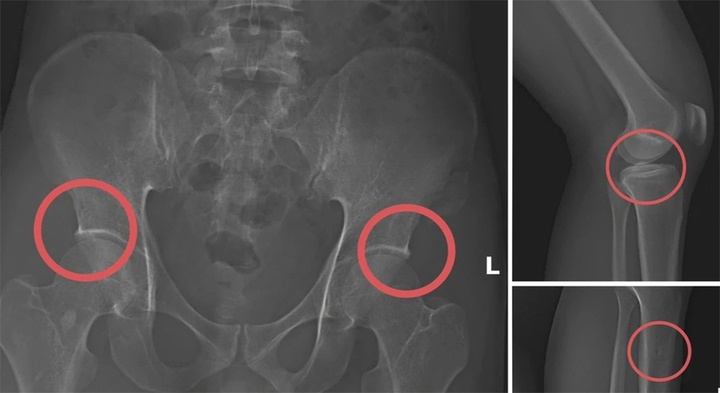

Tại đây, Châu tiêm thuốc mê vào tĩnh mạch của các đối tượng, sau đó dùng búa tác động trực tiếp vào các vùng xương chậu, xương đùi để tạo tổn thương nghiêm trọng.

tu duc vo xuong,  Truc loi bao hiem,   Manulife,  AIA,  Dai-ichi Life,  FWD,  Sun Life,  Chubb Life,  Cong ty Manulife anh 3

Hình ảnh cho thấy các đối tượng tự gây thương tích nhằm trục lợi.